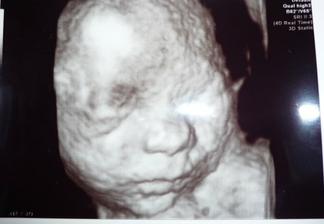

8.2. o 2:55hod sa nam narodil náš chrústik Tomáško, meral 51cm a vážil 3680g,po príchode z pôrodnice vážil 3430g a na poradni v 5 týždnoch meral 59,5cm a vážil 4810g.

Náš vytúžený chrústik Tomáško